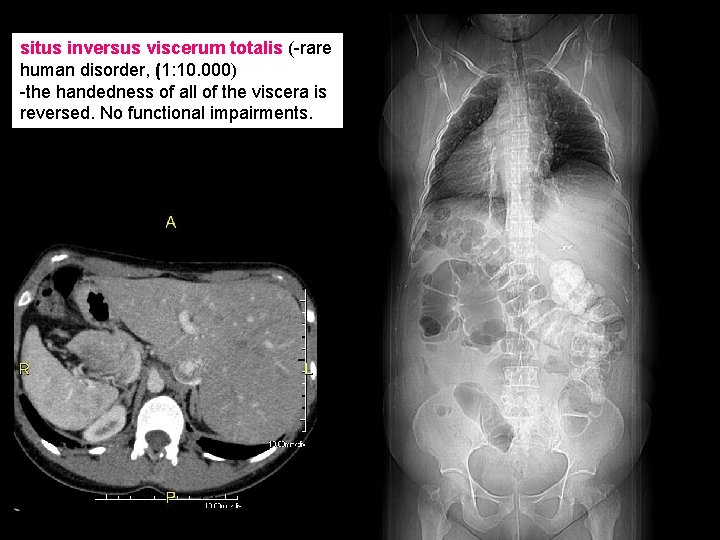

situs inversus viscerum totalis (-rare human disorder, (1: 10. 000) -the handedness of all of the viscera is reversed. No functional impairments.

Medical considerations of LR asymmetry : -situs inversus (1: 10. 000, a complete mirrorimage of asymmetrically positioned organs) Kartagener’s syndrome (1: 30. 000): 1. Chronic bronchiectasis 2. Chronic sinusitis 3. Situs inversus -heterotaxia (situs ambigus) (where each organ makes an independent decision as to its situs), -severe complications right or left isomerism completely symmetrical organs; polysplenia. Kartagener’s syndrome (immotile ciliary syndrome) -hereditary disease -dextrocardia, Kartagener syndrome patients have mutations in DYNEIN genes: --immotile cilia